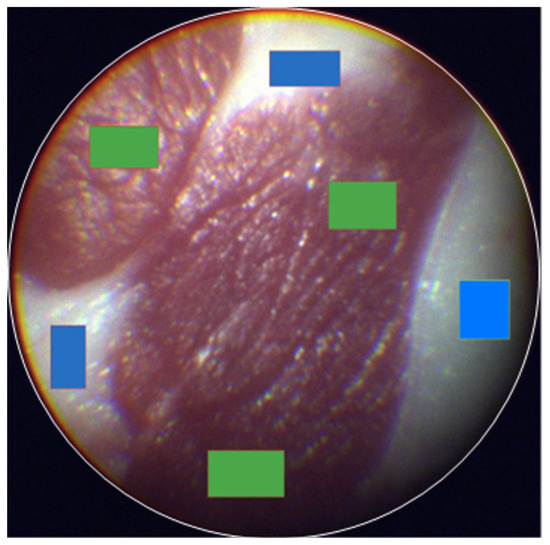

3.2. Tissue Classification Performance of eHSI in Orthotopic Pancreatic Tumors